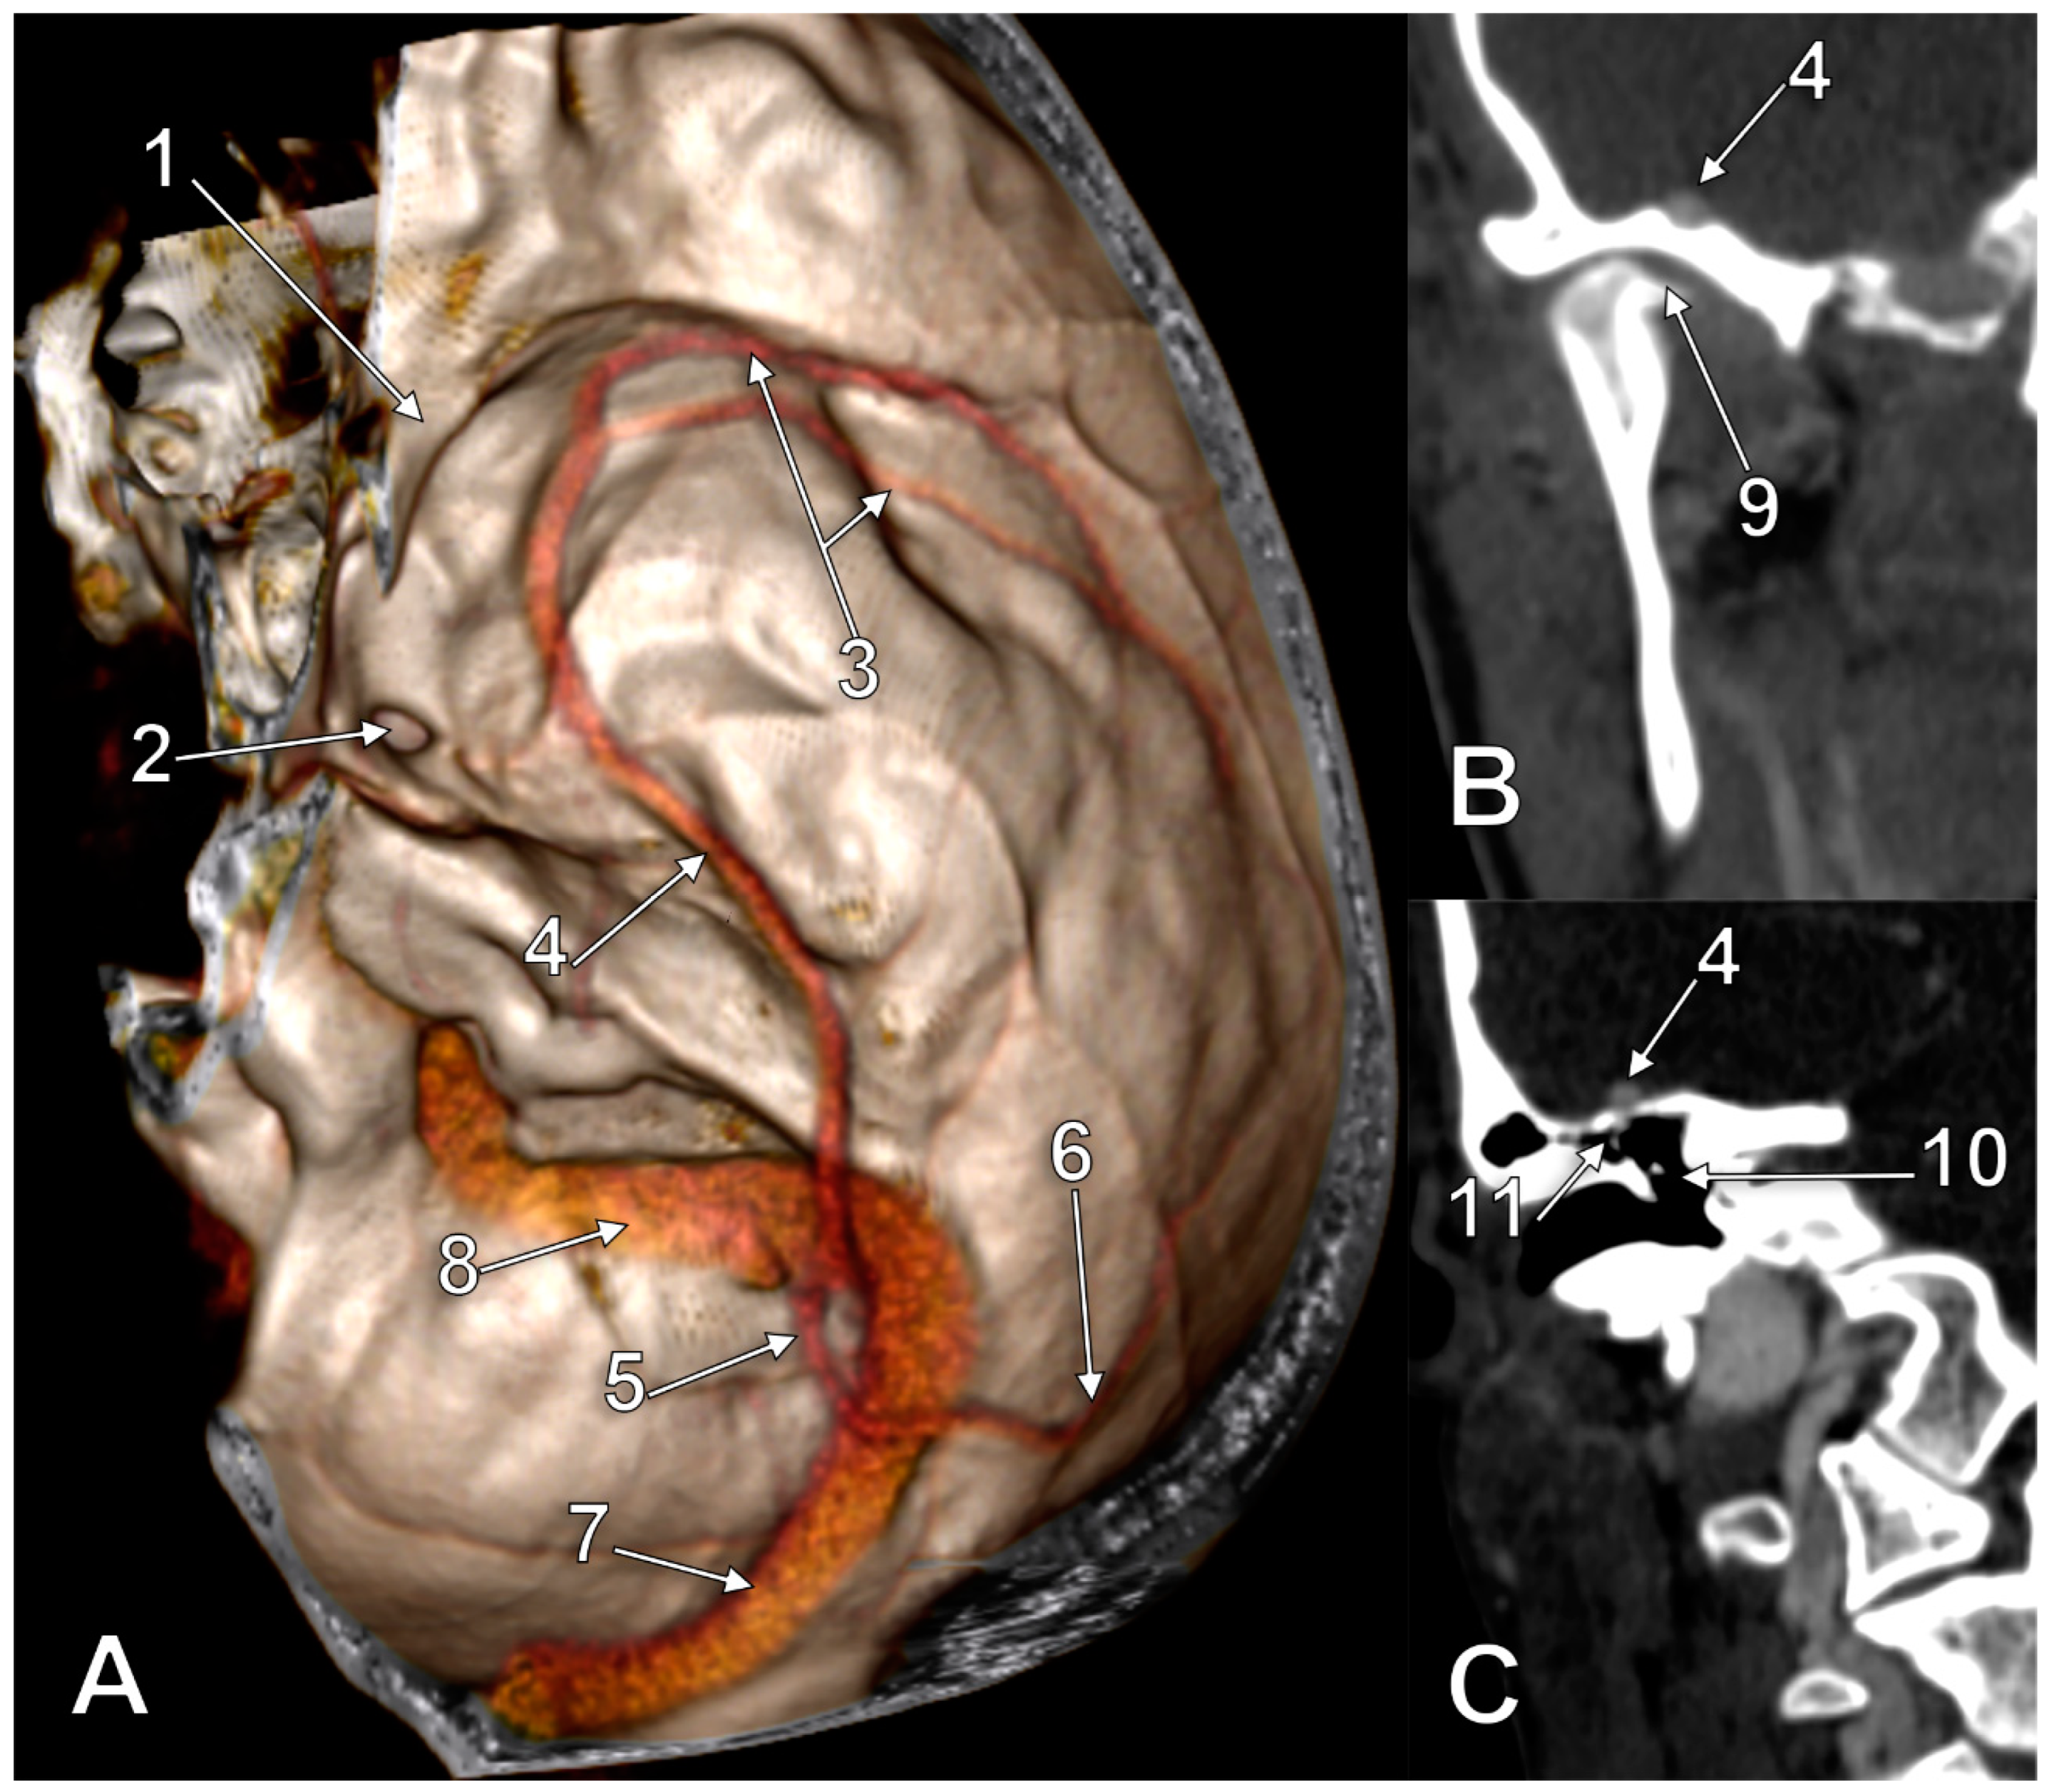

In the third case (Figure 3), the SMCV formed in the Sylvian fissure. Its first segment had a large fenestration, 4.21 cm in length and 0.87 cm in width. The pterion centred the fenestration. The basal course of the unique trunk of this SMCV had alar, squamous, petrous, and mastoid segments. The alar segment was at 1.85 cm lateral to the foramen rotundum and at 1.36 cm lateral to the foramen ovale. Then, it continued over the horizontal part of the temporal squama in a groove extending posteriorly over the tympanic cavum and mastoid antrum. The anterior end of the sulcus of the SMCV was at 1.35 cm lateral to the foramen of Arnold, which, in turn, was at 0.66 cm posterior to the foramen spinosum. On the tympanic roof the SMCV received a tributary from the tympanic cavum. The SMCV finally crossed the petrous ridge and continued with a terminal tentorial segment that joined the lateral end of the transverse sinus at the same point as the Labbé’s vein did on that side.

Figure 3. Three-dimensional volume rendering of (A) a right-fenestrated superficial middle cerebral vein (SMCV) of the basal type, with a tentorial terminal end. (B) Coronal slices through the temporomandibular joint (TMJ) and (C) tympanic cavum. 1. lesser sphenoidal wing; 2. foramen ovale; 3. large fenestration of the SMCV; 4. SMCV on the middle fossa floor; 5. tentorial terminal segment of the SMCV; 6. vein of Labbé; 7. transverse sinus; 8. sigmoid sinus; 9. TMJ; 10. tympanic cavum; 11. tympanic tributary of the SMCV.